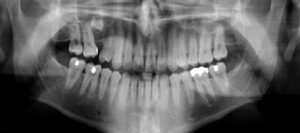

Her çocuk eşsiz olduğu için, diş filmlerinin gerekliliği çocuktan çocuğa farklılık gösterir. Diş filmleri, hastanın şikâyet hikâyesi ve ağız içi ...